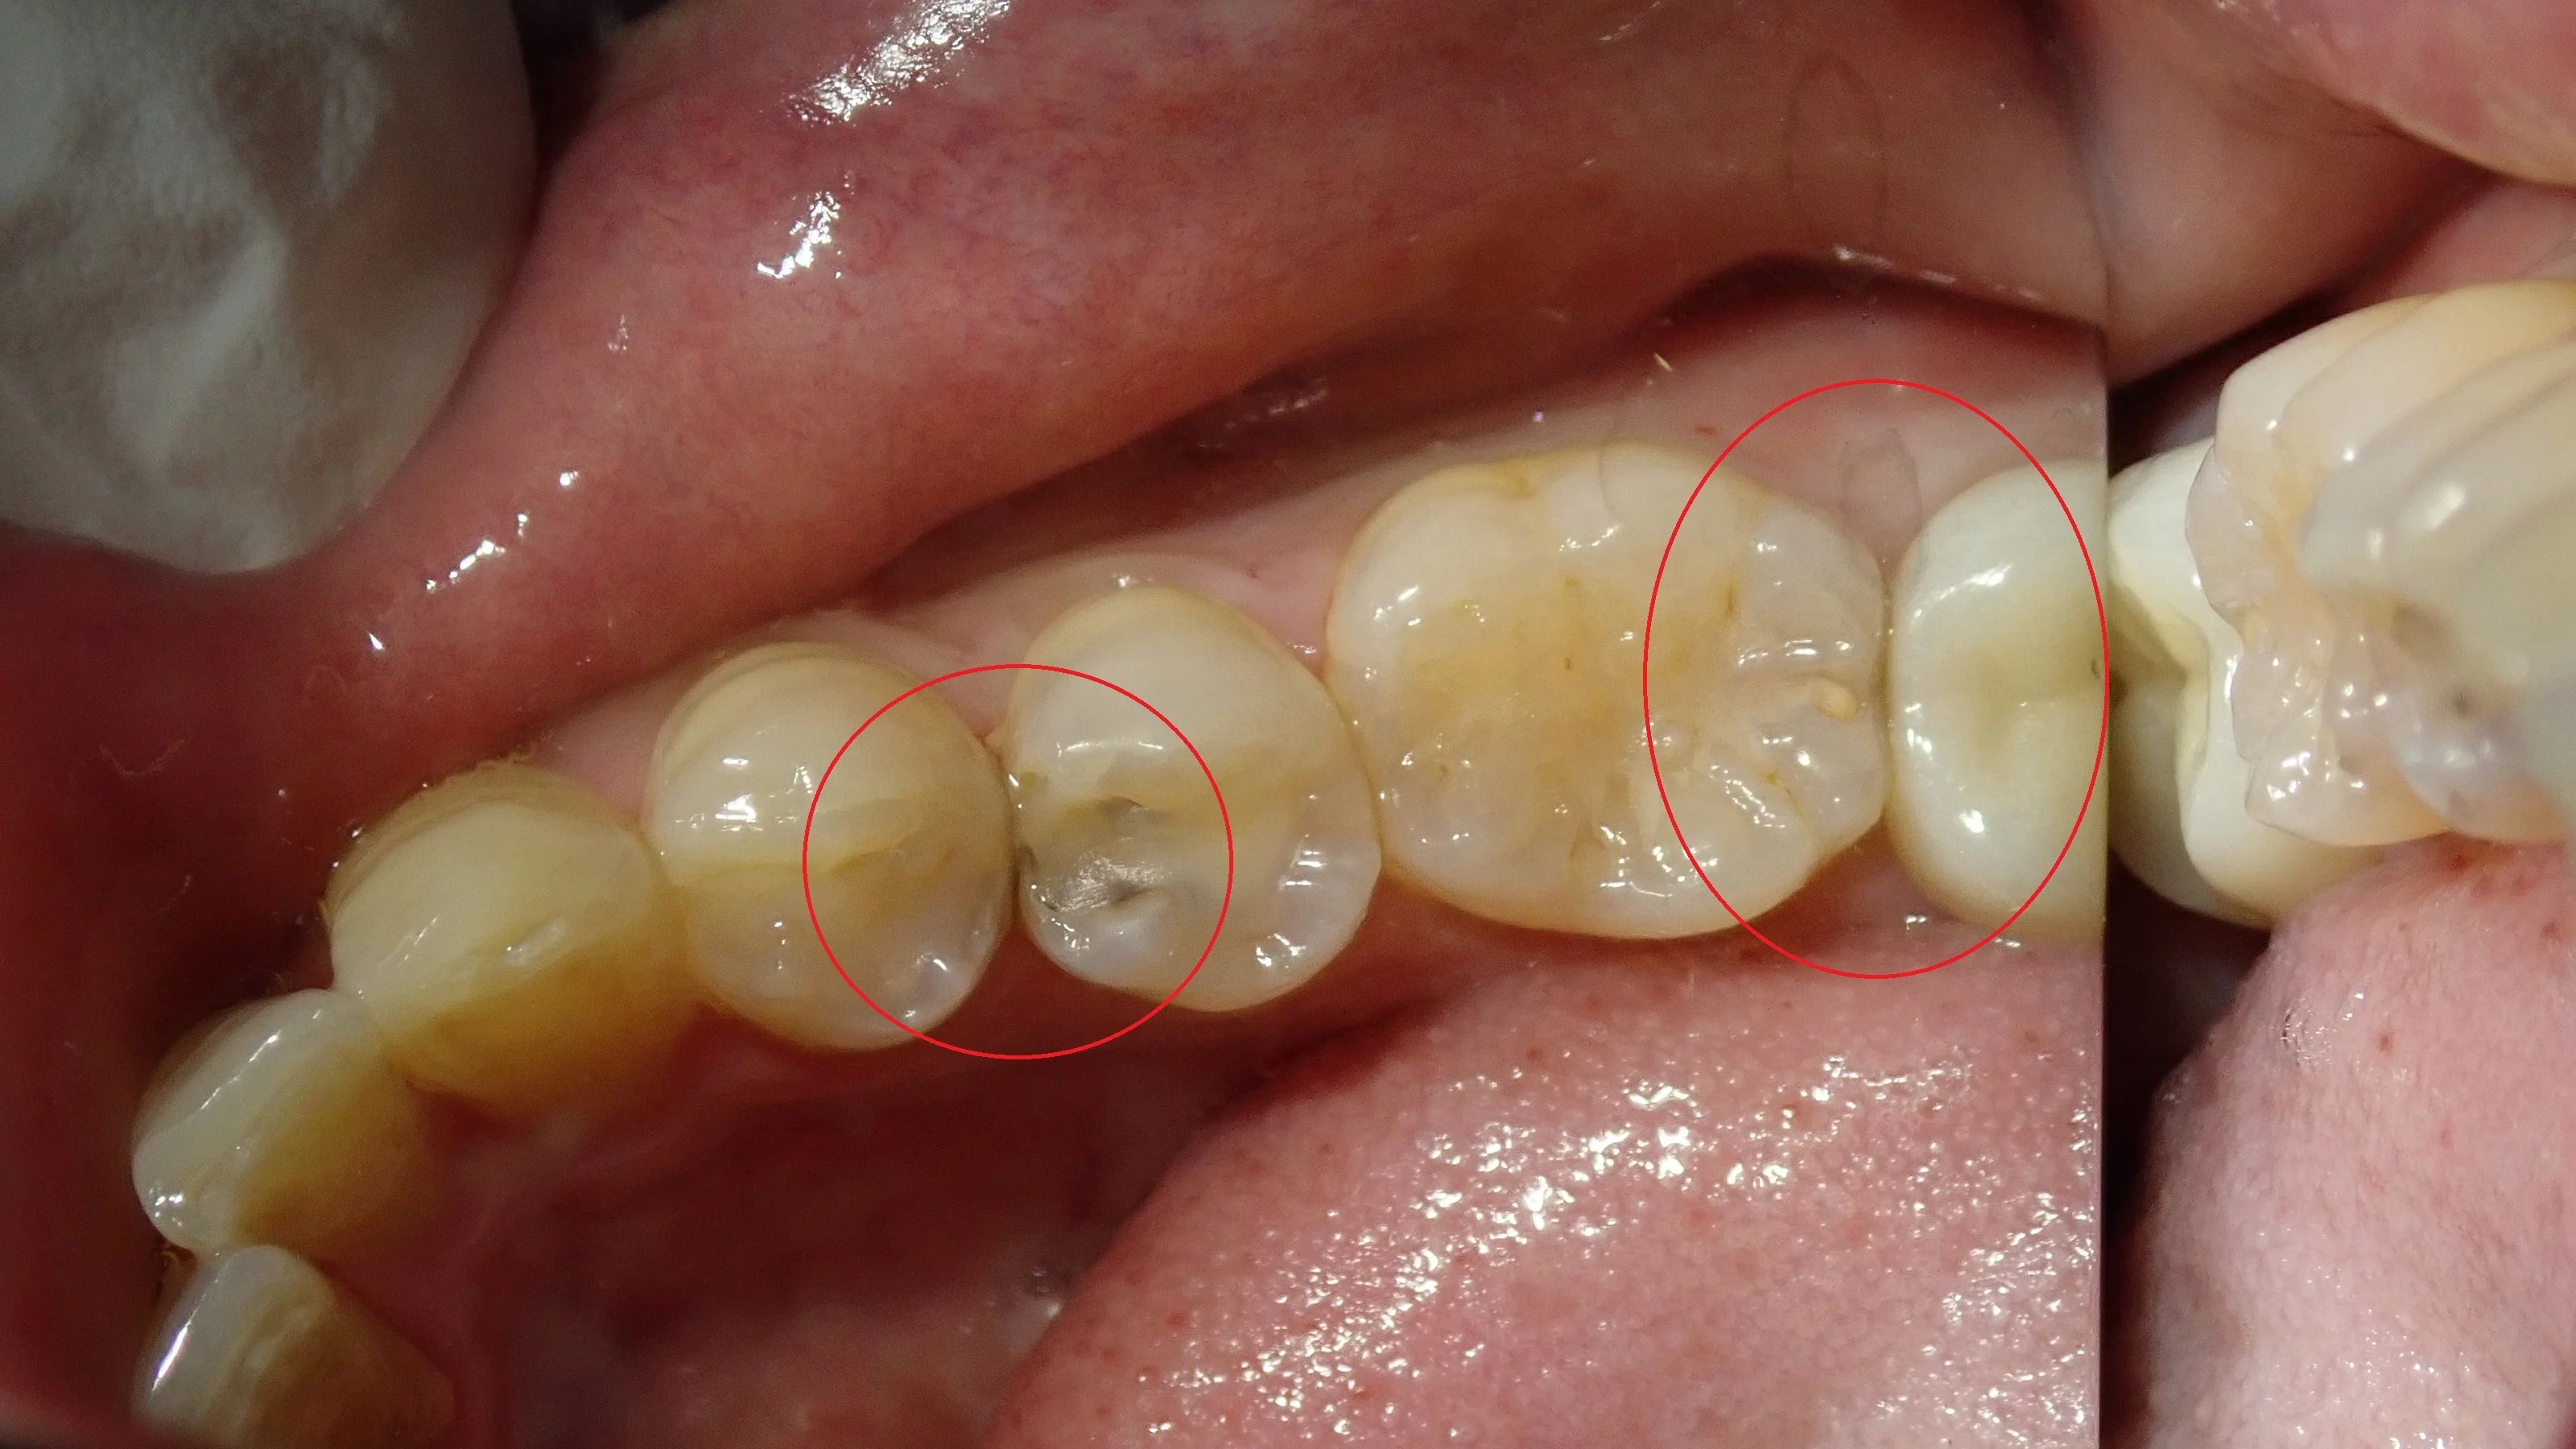

まずは、術前の状態です。

ぱっと見では分かりづらいかもしれませんが、赤丸の場所に虫歯があります。

結構大きく、深い感じですね。

非常に適合が悪い詰め物が入っているので、そのせいで磨きのこしが溜まりやすくなって、結果として虫歯になってしまったと考えられます。